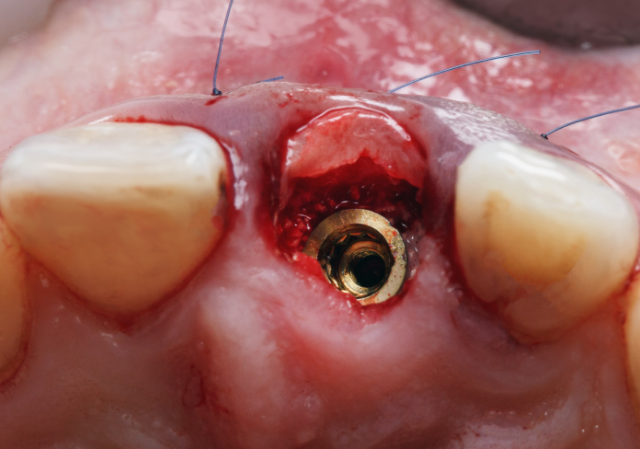

Créez un profil d’émergence adapté pour un rendu naturel de la couronne implantaire.

Offrez à vos patients une base implantaire parfaitement adaptée, prête à accueillir une couronne ou un bridge implantaire avec précision et durabilité. Nos piliers personnalisés permettent de s’affranchir des limites des piliers standards tout en améliorant le rendu final de vos restaurations unitaires ou plurales.